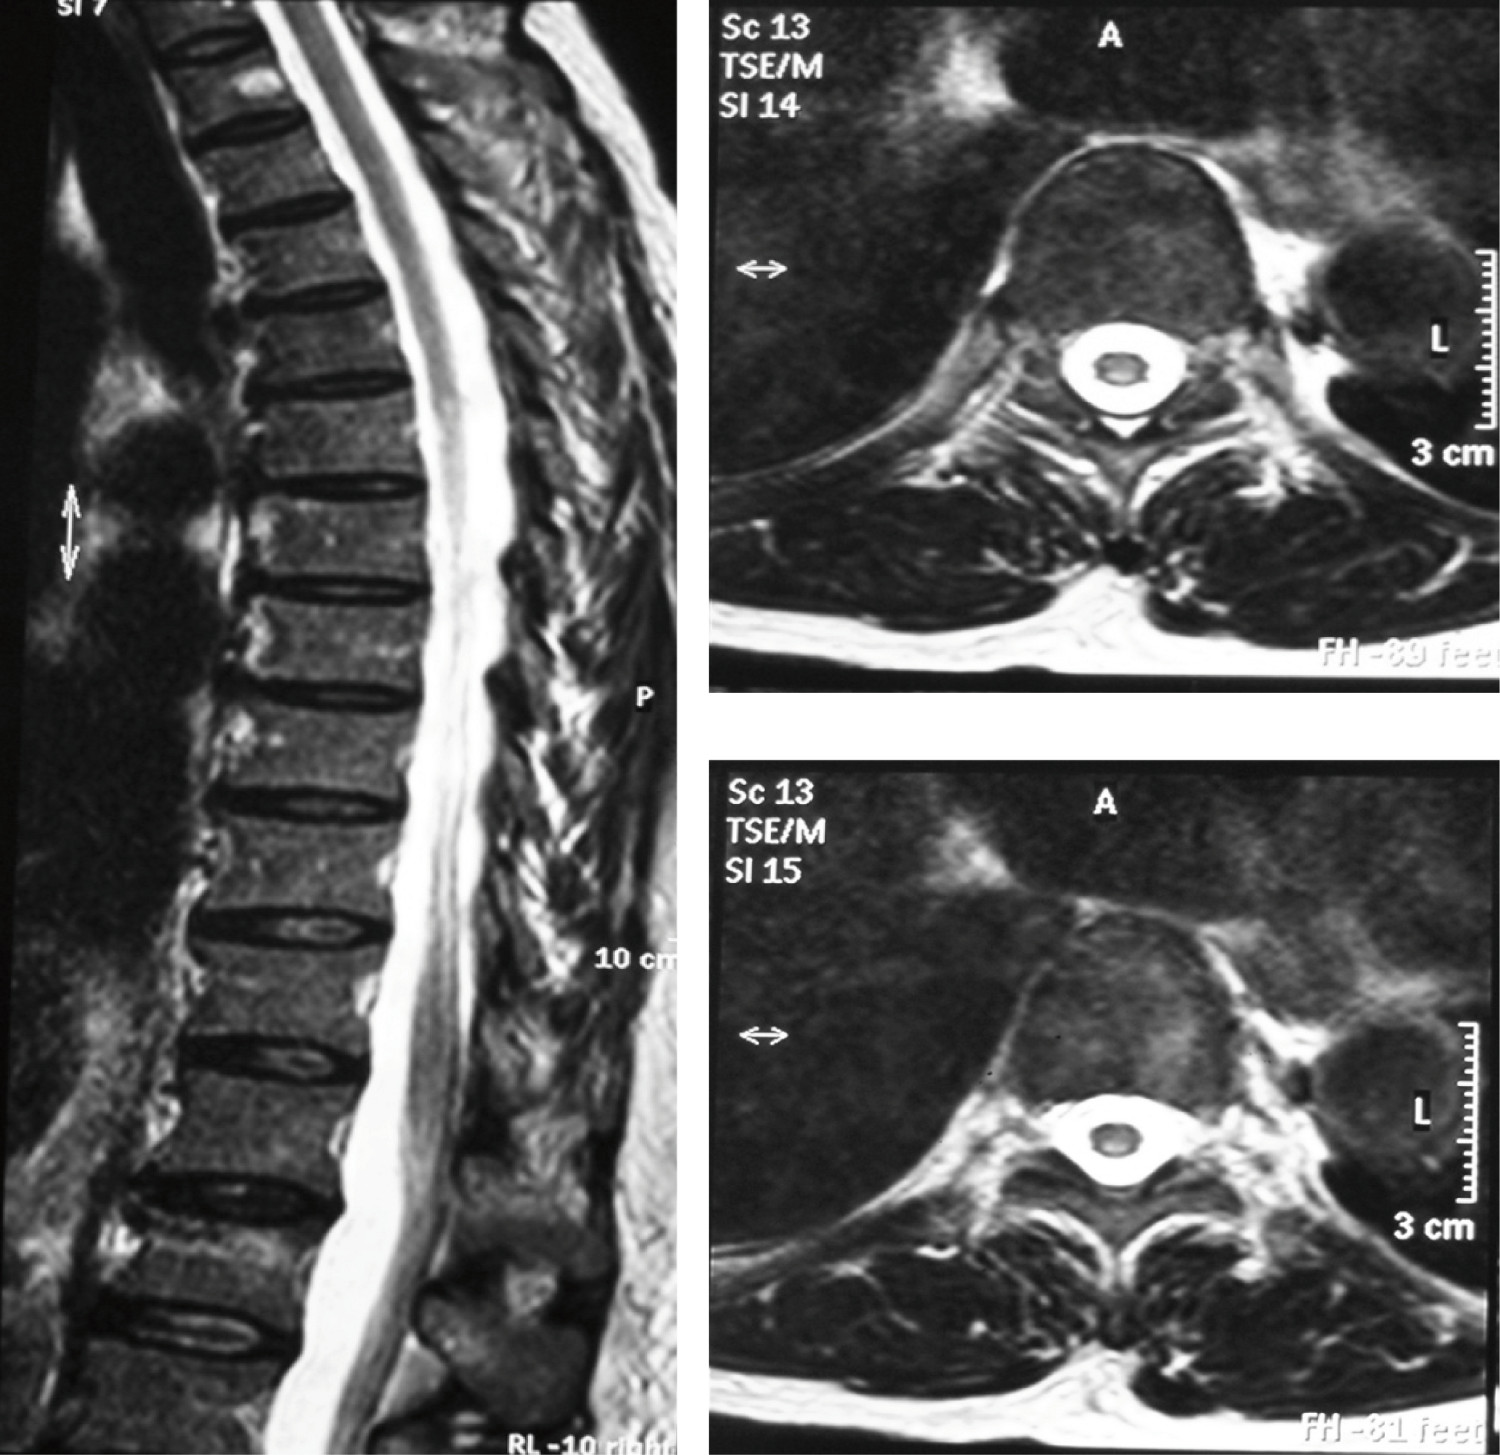

Vitamin B12 deficit diagnosis was performed with hematological manifestations given by macrocytic anemia, neurological manifestations by ataxic gait, and in skin and mucosa by Hunter's glossitis. Because of the neurological alterations in association with ataxic gait and low levels of vitamin B12, nuclear magnetic resonance of the cervical and thoracic spine was requested, which documented images compatible with sub-acute combined degeneration of the spine (Fig. 2).

Figure 2

Cervical and thoracic spine, NMR image in T2 sequence. (A) Sagittal plane, shows hyperintensity in topography of posterior spinal cords from C1 to T11. (B, C) Axial plane at C1 and T8 levels, respectively, evidences hyperintensity symmetrically compromising lateral and posterior spinal cords.

Myelopathy secondary to Cbl deficit, denominated sub-acute combined degeneration of the spine, was one of the cardinal manifestations of the case described along with macrocytic anemia. It is characterized by marrow involvement that affects the posterior and lateral spinothalamic tract, which is initially present at lower cervical and upper thoracic spine level and advances towards the cranial and caudal directions, as well as forward, invading lateral and anterior columns 8 .

Clinical manifestations are given by disorder in deep sensitivity at lower limb level with hypoesthesia, paresthesias, decreased proprioception, and instability in walking with broad support base due to sensory ataxia, which appear symmetrically 7 . In advanced stages tetraparesis or spastic paraparesis and contractures may develop 6 .

Morrow involvement due to Cbl deficit is associated to the presence of different geriatric syndromes like dizziness and syncope, both related to falls, fear of falling, frailty, and failure to thrive 2 . With respect to the case presented, the patient developed gait with characteristics of sensory ataxia, which caused in her a syndrome of falls and fear of falling, with the subsequent restriction in her activities of daily living, leading to frailty and − lastly − functional decline with severe dependence according to Barthel's scale.

When the cervical segments are affected, equivalent symptomatology is observed in the upper limbs, and characteristic presence of Lhermitte's sign, manifested by the patient. This sign is triggered by flexing of the neck, characterized by electrical sensation along the rachis, and it is considered an indicator of demyelization of the posterior spinal cords 7 .

The neuropathological findings in the sub-acute combined degeneration of the spine are given by degeneration of the myelin sheaths, with formation of intramyelinic vacuoles and separation of the myelin sheets. Spongiform demyelization is produced in scattered plates that start at the level of the lateral and posterior columns of the cervical and thoracic spinal cord, which can often affect the anterior columns with axonal degeneration and gliosis in advanced stages of the disease 8 .

The NMR images show focal and symmetric hyperintensity in the posterior half of the spinal cord visible in T2 sequence, explained by increased water content, as illustrated in (Fig. 2). Differential diagnoses for these lesions observed under magnetic resonance include infections (tabes dorsalis, human immunodeficiency virus, and herpes Zoster), neoplasms (lymphoma, paraneoplastic myelopathy), vascular (arterial or venous ischemia, arteriovenous malformation of spinal cord), post-radiation myelitis, multiple sclerosis, acute transverse myelitis, and syringomyelia 8 .